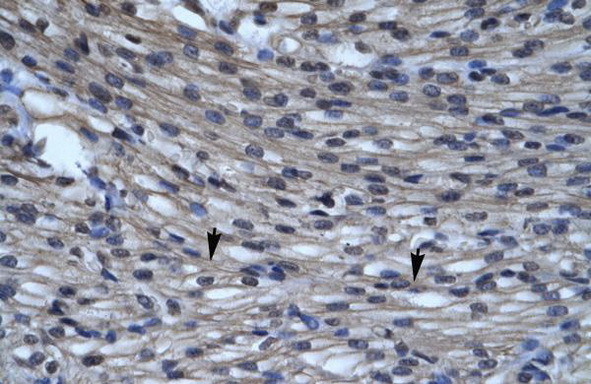

Supportive validation

- Submitted by

- OriGene (provider)

- Main image

- Experimental details

- Human Heart

- Validation comment

- IHC